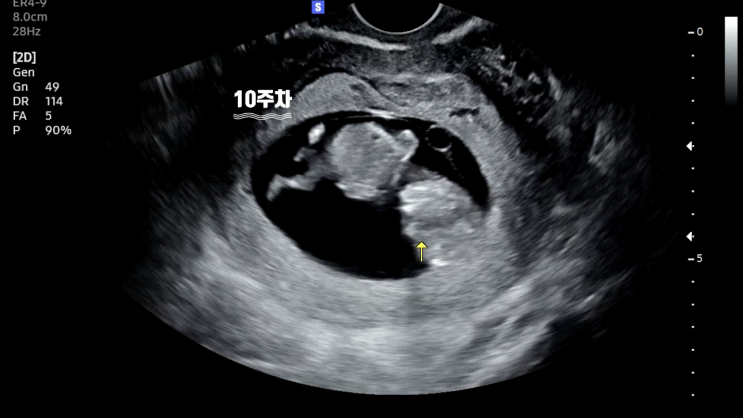

임신 5~9주차 증상 주차별 초음파 사진 첨부

Baby?? 임신 초기 5~9주차 증상 ✅ 임신 5주차: 아기집과 난황 확인 ✅ 임신 6주차: 태아 확인 ✅ 8...